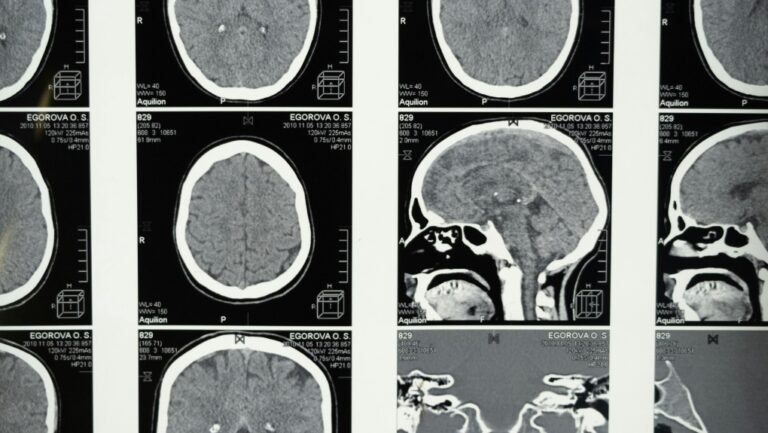

ويأمل المدير العلمي نيل فاسديف داخل مركز تصوير الدماغ في مركز تورنتو للإدمان والصحة العقلية CAMH، أن يكون فريقه على أعتاب القدرة على تشخيص اعتلال الدماغ المزمن CTE لدى شخص حي.

ويكمن أمل فاسديف في دواء إشعاعي جديد، تم تحسينه للكشف عن نوع بروتين تاو الموجود في مرض الاعتلال الدماغي المزمن، وفي الأسابيع المقبلة، سيبدأ فريقه دراسة بحثية كندية على البشر لاختبار فعاليته.